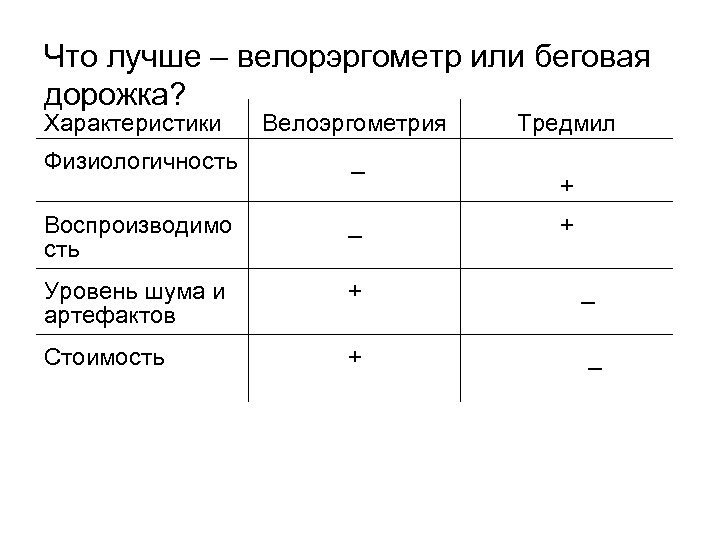

Виды оборудования Что лучше – велорэргометр или беговая дорожка?

Виды оборудования Что лучше – велорэргометр или беговая дорожка?

Что лучше – велорэргометр или беговая дорожка? Характеристики Велоэргометрия Тредмил Физиологичность _ Воспроизводимо сть _ Уровень шума и артефактов + _ Стоимость + _ + +

Что лучше – велорэргометр или беговая дорожка? Характеристики Велоэргометрия Тредмил Физиологичность _ Воспроизводимо сть _ Уровень шума и артефактов + _ Стоимость + _ + +